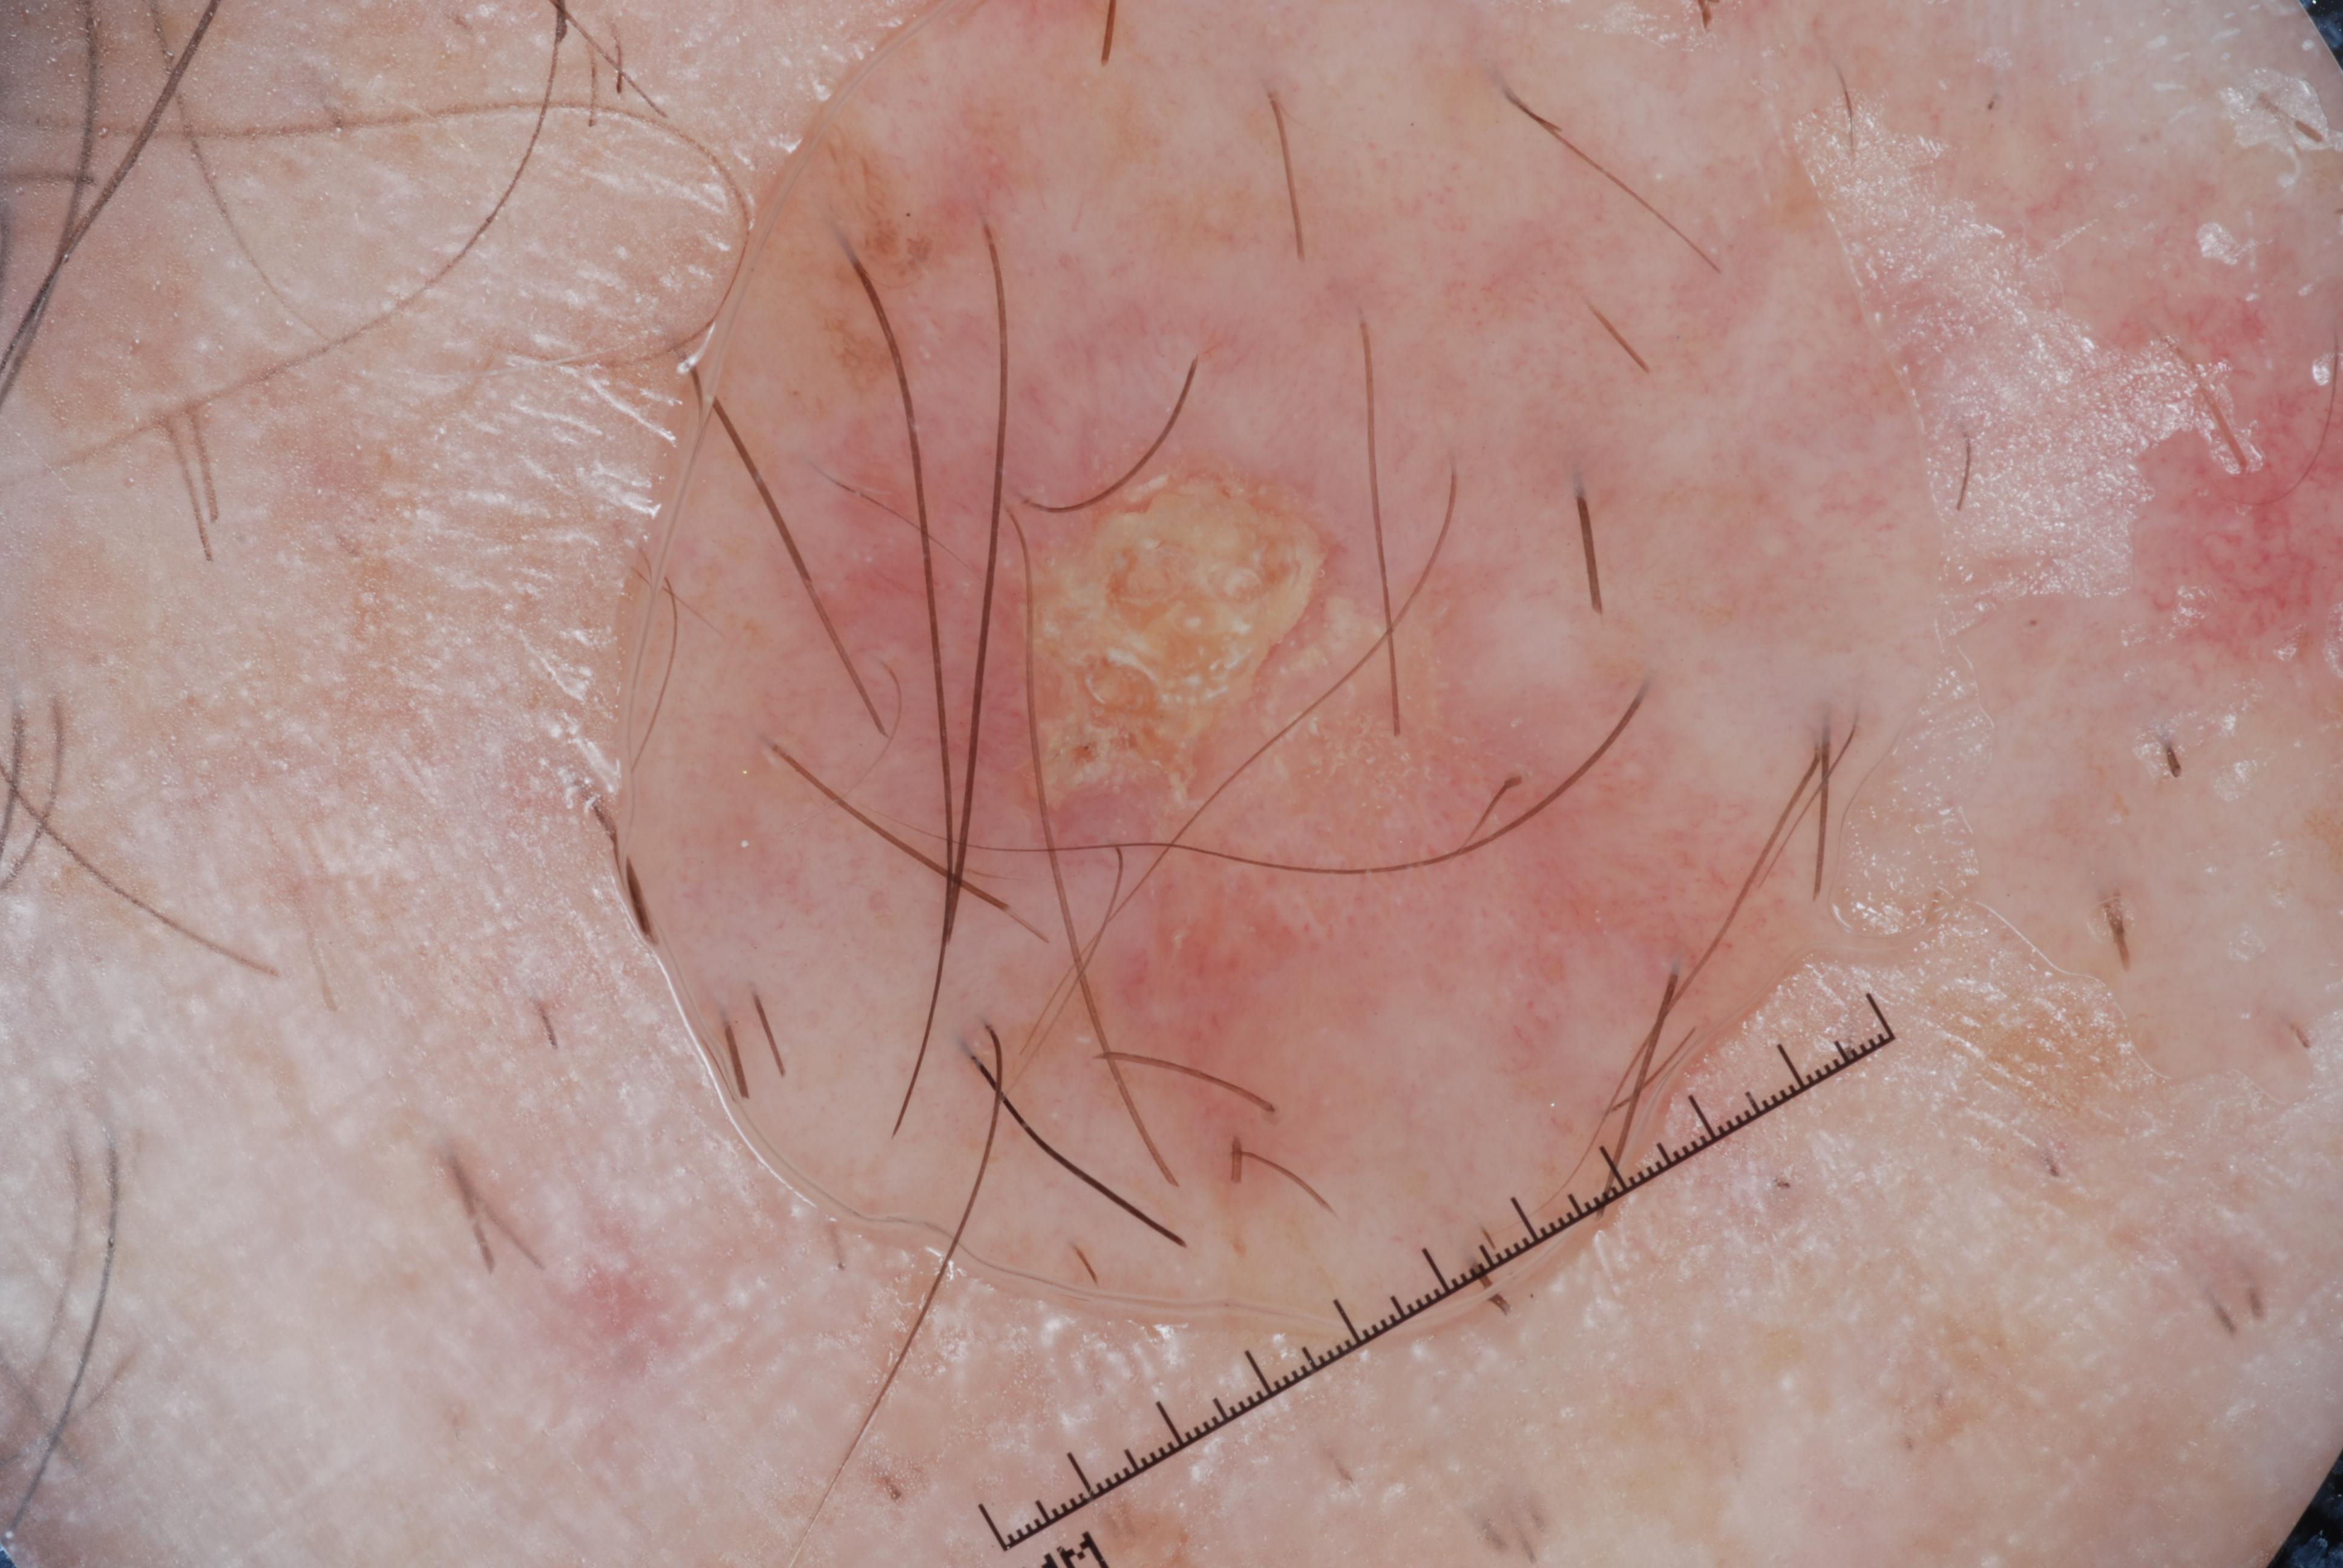

{

"age_approx": 75,

"anatom_site_general": "head/neck",

"concomitant_biopsy": true,

"dermoscopic_type": "contact non-polarized",

"diagnosis_1": "Malignant",

"diagnosis_2": "Malignant melanocytic proliferations (Melanoma)",

"diagnosis_3": "Melanoma in situ",

"diagnosis_confirm_type": "histopathology",

"image_type": "dermoscopic",

"lesion_id": "IL_7473586",

"melanocytic": true,

"sex": "female"